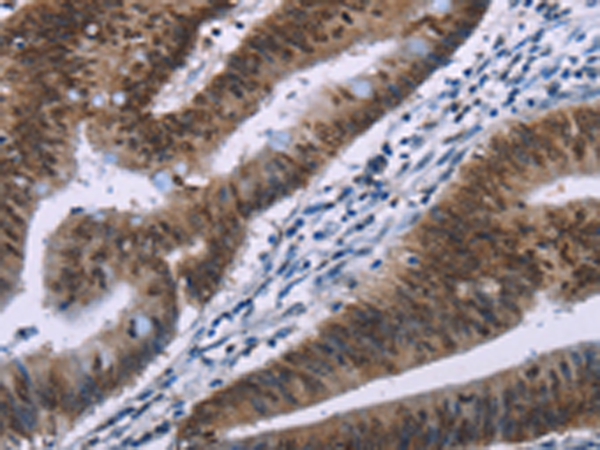

分类: 科研抗体货号: P04027别名: HMG-R, HMGIY, HMGA1A应用: IHC反应种属: Human, Mouse, Rat